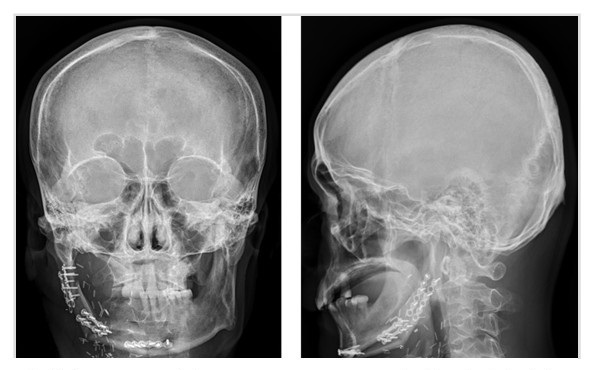

圖示: 平胸手術流程圖說